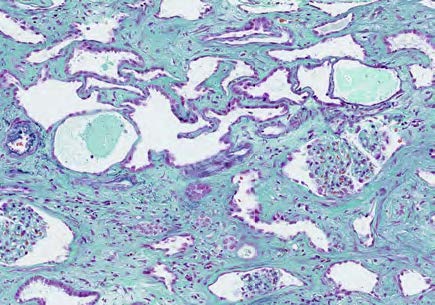

糖尿病の既往のない患者に実施した腎生検で以下の糸球体病変がみられた。鑑別診断に有用でないのはどれか。1つ選べ。

| a | タンパク尿量 |

| b | 喫煙歴 |

| c | 蛍光抗体法 |

| d | 電子顕微鏡所見 |

| e | 尿中ベンスジョーンズ蛋白 |